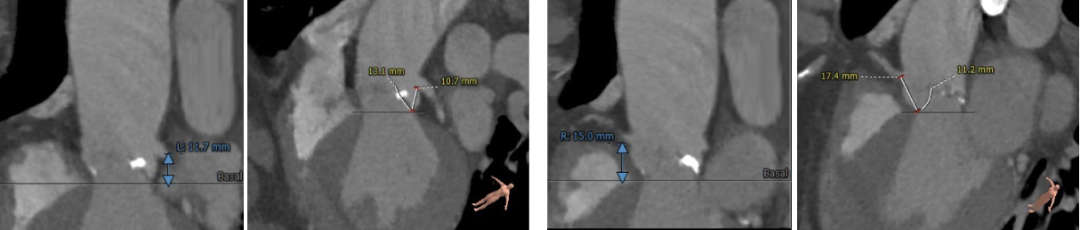

主动脉根部测量

冠脉高度及瓣叶长度测量

瓣环上多平面测量